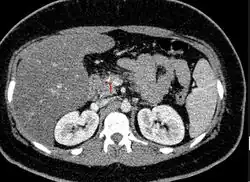

| Axial CT showing multiple calcifications in the pancreas in a patient with chronic pancreatitis | |

On CT scan, pancreatic and bile duct dilatation, atropy of pancreas, multiple calcifications of the pancreas, and enlargement of pancreatic glands can be found.[12]